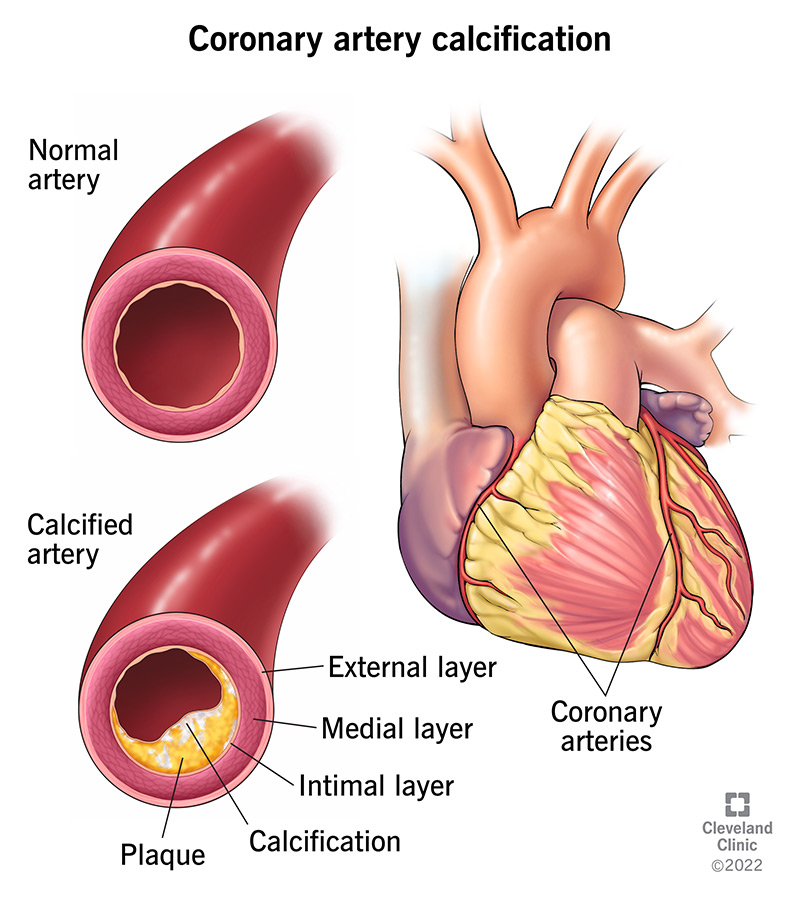

Kidney calcification calcium deposits can also. When blood levels of calcium fall too low, the bones release calcium into the. It involves removing a portion of the pericardium.

Taking medications to reduce high blood pressure taking medications to reduce high cholesterol reducing dietary cholesterol. Low in saturated fat low in refined flour and sugars. Natural remedies for high calcium level while medications for high calcium levels can help, here are some efficient home remedies for the condition: